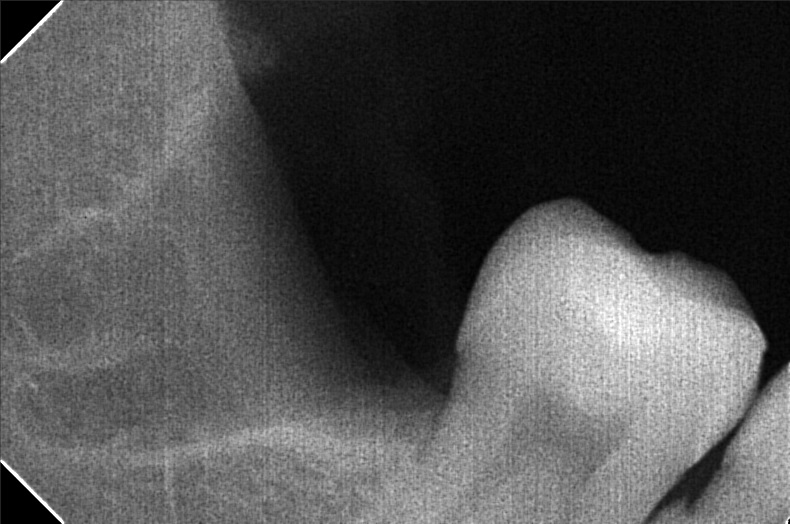

Edit Record Check our patient data records. Add patient information Patient Info Profile picture Last Name First Name Middle Name Birthdate Age Street Barangay City Country Zip Code Contact number Email Procedure 09/08/21- LC 16 occ/ 26 occ/ 25 distal/ 44 DOB+CAOH/ exo 28 with suture and laser 09/18/21 suture removal 28 10/11/21- odontectomy 48 4 sutures/ Rx Co amoxiclav 625mg 01/04/25 OP deep cleaning LC #46 O, M Caoh xray Flexite Denture 5 units upper shade A3 01/14/25 trial 01/25/25 install denture 02/01/25 install brace L 14 Niti L roth 0.22 slot 03/14/25 RW #33 same wire 04/11/25 Adj 16 NiTI L 05/20/25 lingual button #45 18 NITI L 06/10/25 adj 18 niti L nxt visit reattached lingual button #45 07/25/25 same wire RW #45 w/ chain to #46 LC #31 M 08/22/25 adj 16 SS L 11/20/25 adj same wire 12/18/25 16 & 18 SS lower - double wiring Button #44 01/7/26- same wire. IPR 44, 45 derotate 45 1/23/26 adj same wire L, button on #46 chain #33 to 35 2/5/26 adj same wire 3/5/26 adj same wire 04/08/26 adjustment re-attached button 04/29/26 adjustment attach 2 button #44|#45 File stephanie_panoramic.jpg File 2 robete48.jpg File 3 robete48-2.jpg File 4 File 5 File 6 File 7 File 8 File 9 File 10 File 11 File 12 File 13 File 14 File 15 File 16 File 17 File 18 File 19 File 20 Retain Record Retain Record Yes No Save Your Changes